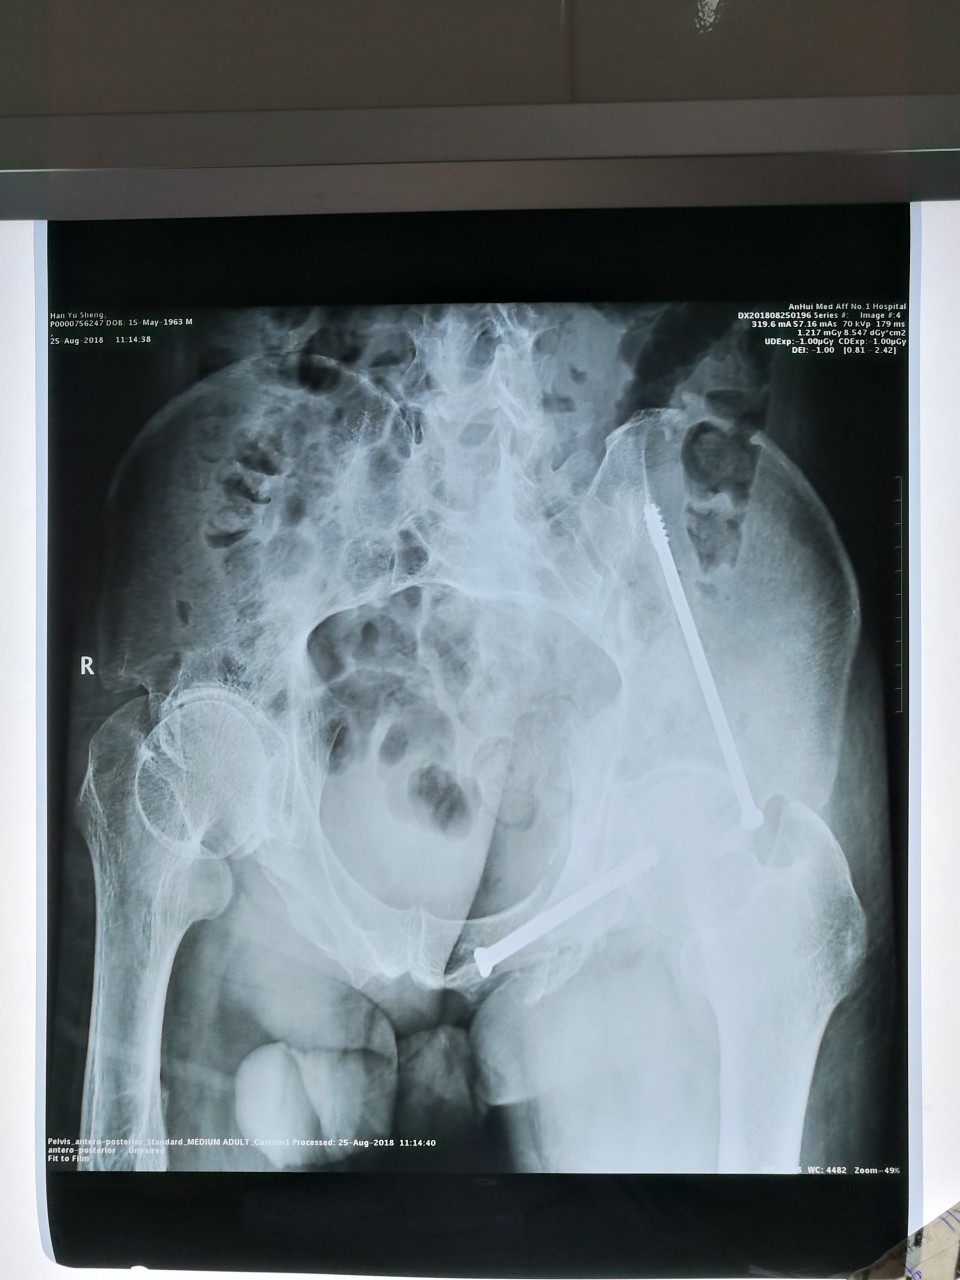

55岁的患者韩某因外伤致骨盆骨折,多发肋骨骨折,胸腔积液,全身多处外伤。入院后,经我院创伤骨科及胸外科共同抢救保住生命,经过2周的救治病情得到初步控制,必须稳定骨盆才能更好地康复。但传统骨盆手术不仅创伤大,出血多,手术时间也长,对于该患者来说是存在极大的风险,创伤骨科王刚副主任医师团队在综合评估后,决定采用最新的“微创骨盆矫正复位系统”先对移位的骨盆进行复位,再配合我院现有的“天玑”骨科机器人为该患者行微创螺钉固定,不仅可以极大减少术中出血,缩短手术时间,也可为病人快速康复奠定基础。

在各方积极配合下,手术非常顺利,微创骨盆复位系统与“天玑”骨科机器人配合天衣无缝,手术用时仅2小时,仅有几个1厘米左右的切口,几乎没有出血,甚至预计的输血都不需要。术后该患者在医生帮助下已开始进行床上翻身、屈伸髋膝等康复锻炼。